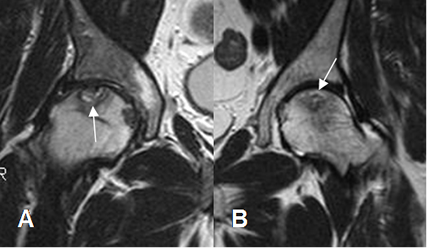

Fig 82. Osteonecrosis.

A y B: RM coronal en T2. Signo del doble halo. Reborde hiperintenso en T2, específico de osteonecrosis.